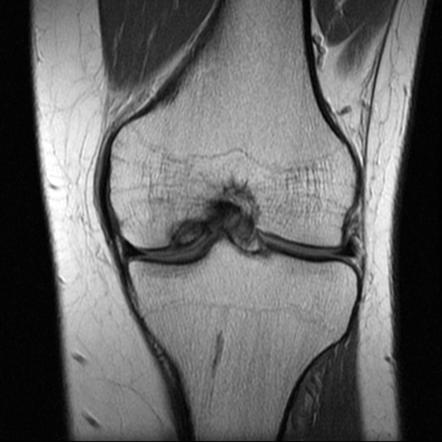

Kıkırdak yaralanmalarının tanısı için öncelikle hastanın şikayeti ve hikayesi öğrenilir. Sonrasında ayrıntılı bir muayene yapılır ve gerekirse röntgen, MRG, MR-artrografi ve artroskopi gibi görüntüleme yöntemlerine başvurulur.

| Eklem kıkırdağında bozulma olan dizin; A. Röntgen filmi, B. MR görüntüsü |